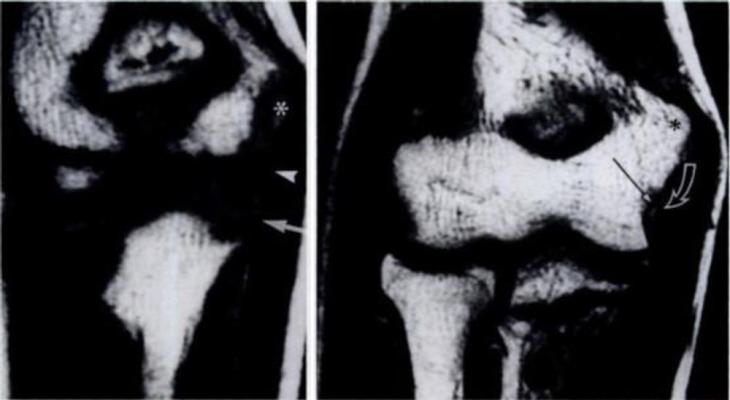

In this retrospective study, the researchers reviewed elbow MRI exams from 130 youth players (18 years of age and younger) being evaluated for elbow pain. MRI is an ideal method for identifying joint problems, because it can non-invasively show cross-sectional details of soft tissues (cartilage, tendons and ligaments) and bone.

The most common MRI findings in skeletally immature players included fluid build-up around the joint, stress injuries near the growth plate, fractures, and osteochondritis dissecans (OCD) lesions, where a piece of bone and the overlying cartilage is injured and can detach, leading to reduced range of motion and risk for premature osteoarthritis in adulthood.

Injuries that required surgery included intra-articular bodies (small fragments inside the joint), and unstable OCD.

“In terms of the skeletally immature children, 9 patients (11%) had intra-articular bodies, and 19 patients (22%) had OCD lesions,” Patel said.